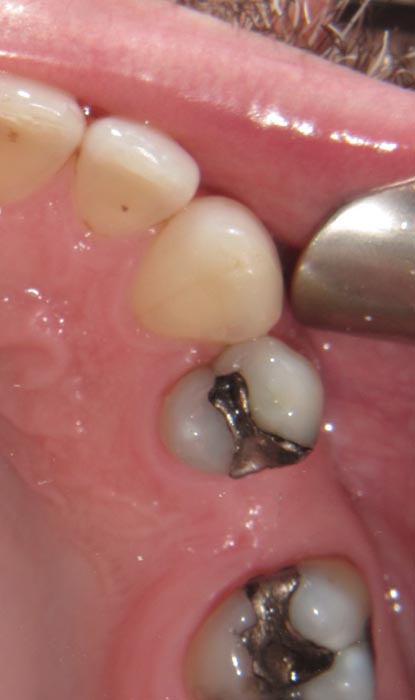

Case 2

A 52-year-old patient presented with failing composite on #26. We see this often; it indicates microleakage at the material/tooth interface because of degradation of the bonding agent.

• Figure 7

• Figure 8

• Figure 9

• Figure 10